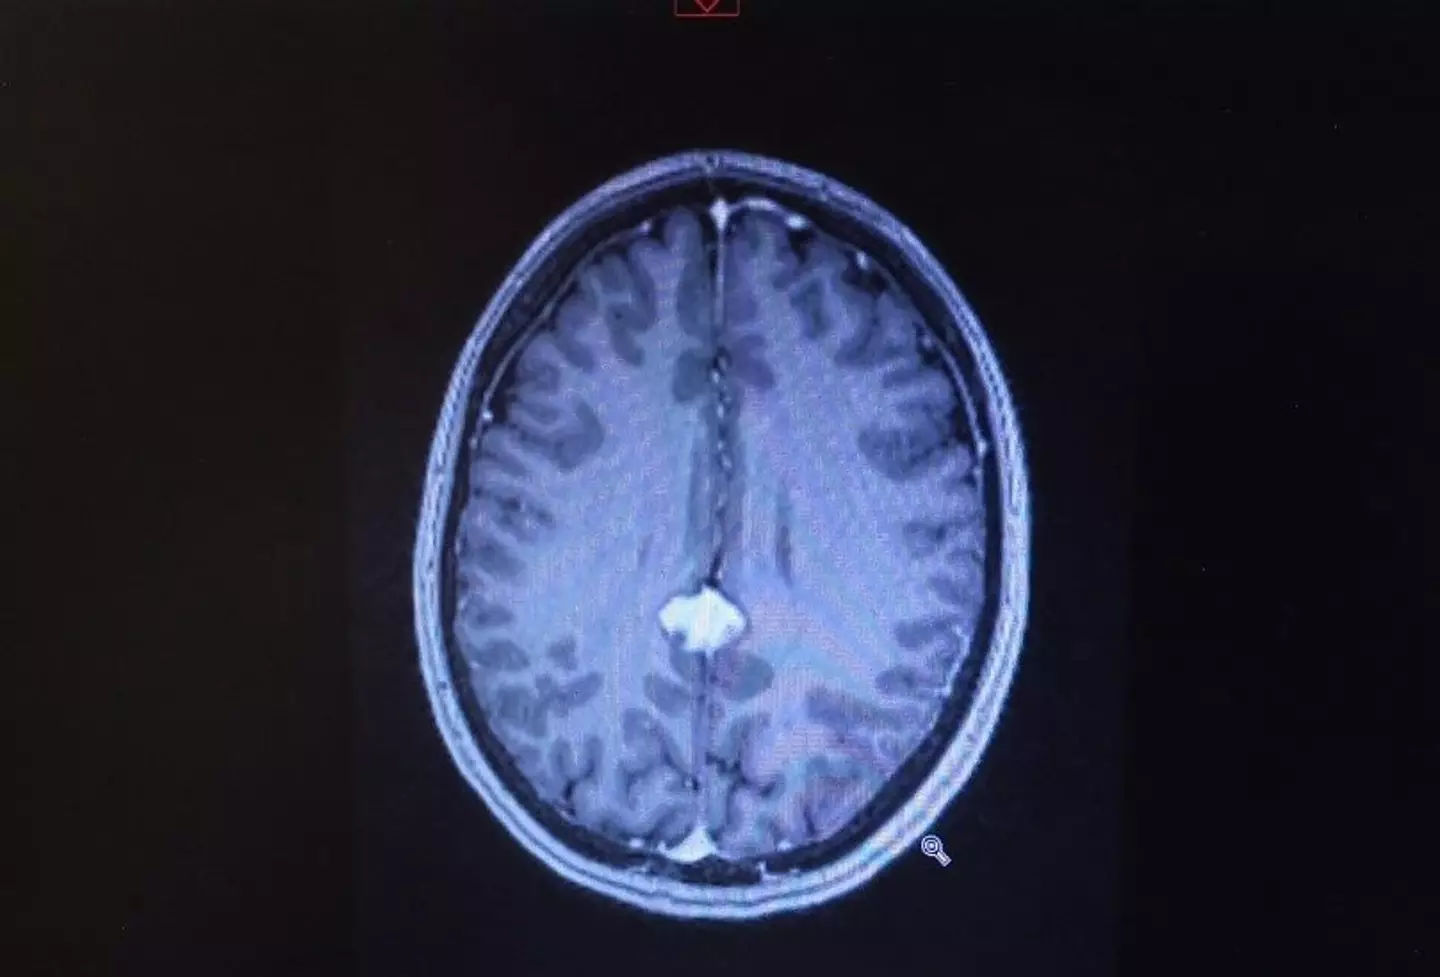

Technically, April had been diagnosed with a posterior falcine meningioma, a low-grade tumour which is located deep in the centre of her brain.

Because of this factor, the mum - who has one teenage daughter, Abby - was placed on watch and wait, and instructed to go for brain scans every six months.

Not only did she have a mass on her brain, but doctors could tell straight away that surgery upon the tumour was no longer an option, due to its positioning.